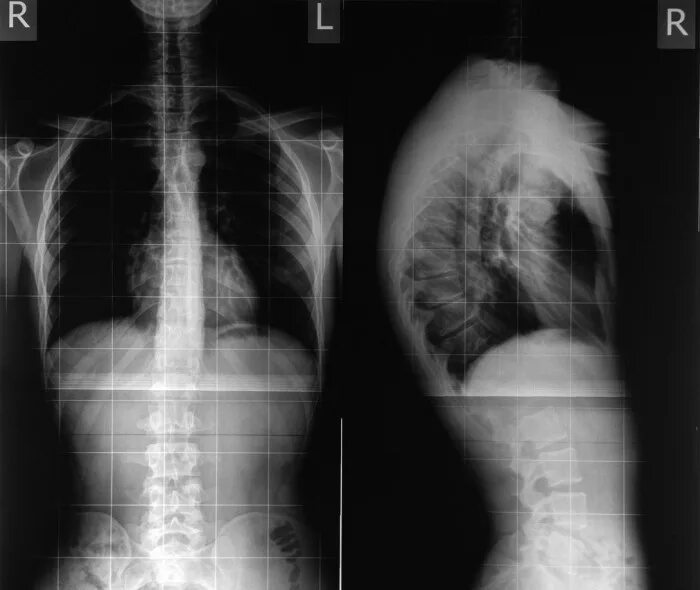

Болезнь шейермана мау что